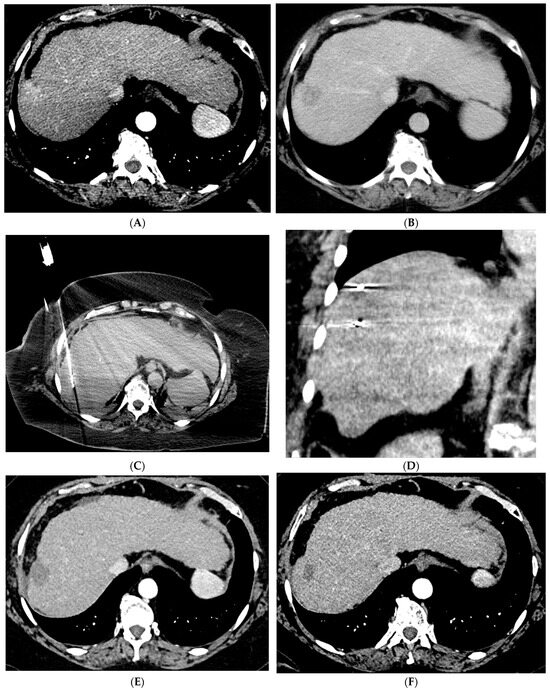

Figure 2. 88-year-old woman with HCC on a background of cirrhosis secondary to autoimmune hepatitis treated with conventional TACE. (A) Arterial phase MRI showing a 2.2 cm arterially enhancing lesion in hepatic segment 8. (B) Delayed phase MRI showing washout of the lesion. (C) Intraprocedural CTA demonstrating supply to the hypervascular lesion from the segment 8 arterial branch. (D) Post procedure non-contrast CT demonstrating the ethiodized oil deposition within the tumor and surrounding segment 8 parenchyma. (E) Follow up arterial phase MRI one month after treatment demonstrating no arterial enhancement within the treated lesion consistent with complete response.

Figure 3. 73-year-old man with non-cirrhotic HCC treated with 90Y radiation segmentectomy. (A) Arterial phase MRI showing a 4 cm arterially enhancing lesion in hepatic segment 5. (B) Delayed phase MRI showing washout of the lesion. (C) Intraprocedural CTA demonstrating supply to the posterior aspect of the mass from one of the segment 5 branch arteries. (D) Intraprocedural CTA demonstrating supply to the anterior aspect of the mass from a separate segment 5 branch artery. The Y90 dose was delivered as a split dose between these two arteries. (E) Follow up arterial phase MRI 3 months after treatment demonstrates wedge-shaped post-treatment changes in hepatic segment 5 with expected parenchymal enhancement and capsular retraction with no residual enhancement of the targeted tumor. (F) Follow up delayed phase MRI demonstrates no wash-out of the enhancing parenchyma to suggest residual viable tumor, consistent with complete response.

TACE is the mainstay of treatment in intermediate stage (BCLC-B) HCC. Conventional TACE (cTACE) is performed with a combination of ethiodized oil and chemotherapy, in the US most commonly doxorubicin, either alone or in combination with mitomycin and cisplatin, followed by an embolic agent such as polyvinyl alcohol (PVA) or a gelatin sponge (Figure 2). TACE with drug-eluting beads (DEB-TACE) uses doxorubicin-loaded microspheres as a simultaneous drug-delivery and embolic agent. In the PRECISION V trial, the two techniques were compared, and results demonstrated a decrease in systemic side effects with DEB-TACE with similar survival rates [27]. Another study by Li et al. similarly showed a decrease in complications and prolonged interval between treatments with DEB-TACE [28]. In a more recent study, the PRESIDENT trial, cTACE was again compared to the more modern techniques of DEB-TACE [29]. The results demonstrated that the cTACE cohort had higher rates of complete response at 1- and 3-month time points (84.2%, 75.2%) versus the DEB-TACE group (35.7%, 27.6%). However, the cTACE group had significantly higher rates of adverse events attributed to post embolization syndrome including fever, fatigue, malaise, abdominal pain, anorexia, and lab abnormalities including elevated bilirubin, AST, ALT, and hypoalbuminemia [29].

Variations in TARE include radiation segmentectomy and lobectomy [10]. In patients in which resection or ablation is not feasible, radiation segmentectomy can offer an ablative level treatment dose to lesions confined to less than two segments while sparing the remaining normal liver parenchyma [10] (Figure 3). The RASER trial demonstrated that radiation segmentectomy in patients with a solitary HCC tumor in an unfavorable location for ablation resulted in high rates of complete response (24/29 patients, 83%) with low rates of adverse events [38]. In the DOSISPHERE-01 study, patients with unresectable HCC were randomized to either standard dosimetry (120 ± 20 Gy) to the diseased lobe or personalized dosimetry (>205 Gy) to the index lesion. Patients in the personalized dosimetry group had significantly higher rates of objective response to therapy with similar rates of adverse effects [39]. Radiation lobectomy is yet another application of 90Y that involves administering a higher dose to the diseased lobe of the liver, with the goal of inducing tumor death and atrophy of the diseased lobe with resultant compensatory hypertrophy of the normal lobe. This concept can allow patients who would not otherwise be candidates for surgical resection due to a small future liver remnant (FLR) to be able to undergo resection [10].